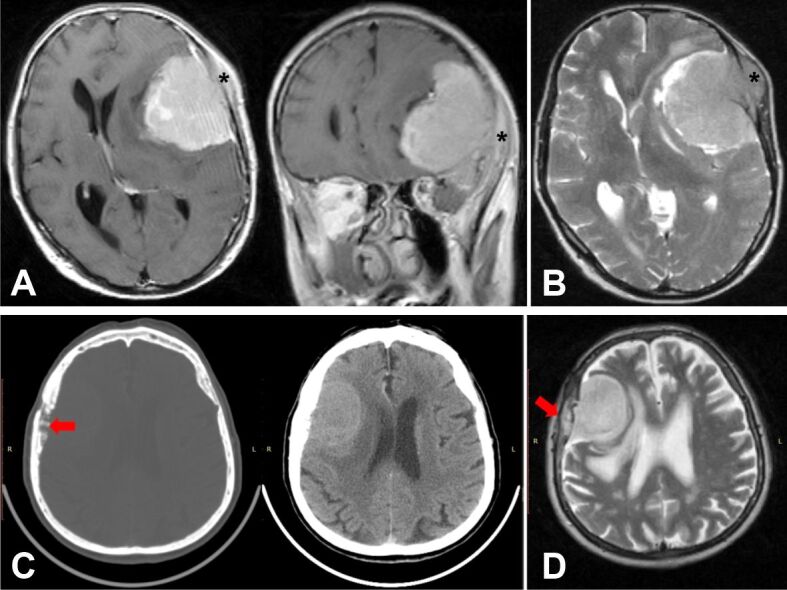

Patients, materials and methods: Out of 81 patients with AMs followed over a period of five years, we identified nine patients with bone invasion. We analyzed their demographic, clinical, imaging, and pathological characteristics, such as age, gender, radiological aspects, morphological features, extent of resection, recurrence rate, and PFS over a follow-up period of 60 months. Bone invasion was determined based on preoperative, surgical, and pathological reports.

Results: Out of the nine patients with bone invasion, four had convexity meningiomas, four had parasagittal meningiomas and one had a falcine meningioma. Regarding tumor recurrence∕progression, most patients (n=6) recurred within the first 24 months after surgery. Our study showed that the early recurrence/progression of tumor (at 12 months) correlated with extensive presence of malignancy criteria, especially with the presence of 15-18 mitoses∕10 high-power fields, as well as with large foci of spontaneous necrosis, but also with tumor bone infiltration, extensive bone lamellae destruction, and tumor infiltration of adjacent muscle with its atrophy due to tumor compression. Patients with bone invasion had a PFS of 29.3 months, compared to patients without invasion who had a higher PFS (49.3 months). Significant statistical associations were observed between bone invasion and tumor recurrence (p=0.002) and PFS (p=0.004).